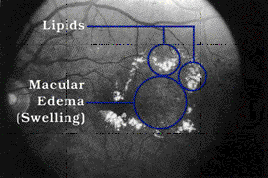

| Diabetic retinopathy occurs when diabetes damages the tiny blood vessels in the retina. At this point, most people do not notice any changes in their vision. Some people develop a condition called macular edema. It occurs when the damaged blood vessels leak fluid and lipids onto the macula, the part of the retina that lets us see detail. The fluid makes the macula swell, blurring vision. As the disease progresses, it enters its advanced, or proliferative, stage. Fragile, new blood vessels grow along the retina and in the clear, gel-like vitreous that fills the inside of the eye. Without timely treatment, these new blood vessels can bleed, cloud vision, and destroy the retina. Who is at risk for this disease? All people with diabetes are at risk--those with Type I diabetes (juvenile onset) and those with Type II diabetes (adult onset). During pregnancy, diabetic retinopathy may also be a problem for women with diabetes. It is recommended that all pregnant women with diabetes have dilated eye examinations each trimester to protect their vision. What are its symptoms? Diabetic retinopathy often has no early warning signs. At some point, though, you may have macular edema. It blurs vision, making it hard to do things like read and drive. In some cases, your vision will get better or worse during the day. View of boys by person with normal vision. View of boys by person with diabetic retinopathy. |

| As new blood vessels form at the back of the eye, they can bleed (hemorrhage) and blur vision. The first time this happens it may not be very severe. In most cases, it will leave just a few specks of blood, or spots, floating in your vision. They often go away after a few hours. These spots are often followed within a few days or weeks by a much greater leakage of blood. The blood will blur your vision. In extreme cases, a person will only be able to tell light from dark in that eye. It may take the blood anywhere from a few days to months or even years to clear from the inside of your eye. In some cases, the blood will not clear. You should be aware that large hemorrhages tend to happen more than once, often during sleep. How is it detected? Diabetic retinopathy is detected during an eye examination that includes: Visual acuity test: This eye chart test measures how well you see at various distances. Pupil dilation: The eye care professional places drops into the eye to widen the pupil. This allows him or her to see more of the retina and look for signs of diabetic retinopathy. After the examination, close-up vision may remain blurred for several hours. Ophthalmoscopy: This is an examination of the retina in which the eye care professional: (1) looks through a device with a special magnifying lens that provides a narrow view of the retina, or (2) wearing a headset with a bright light, looks through a special magnifying glass and gains a wide view of the retina. Tonometry: A standard test that determines the fluid pressure inside the eye. Elevated pressure is a possible sign of glaucoma, another common eye problem in people with diabetes. Your eye care professional will look at your retina for early signs of the disease, such as: (1) leaking blood vessels, (2) retinal swelling, such as macular edema, (3) pale, fatty deposits on the retina--signs of leaking blood vessels, (4) damaged nerve tissue, and (5) any changes in the blood vessels. Should your doctor suspect that you need treatment for macular edema, he or she may ask you to have a test called fluorescein angiography. In this test, a special dye is injected into your arm. Pictures are then taken as the dye passes through the blood vessels in the retina. This test allows your doctor to find the leaking blood vessels. How is it treated? There are two treatments for diabetic retinopathy. They are very effective in reducing vision loss from this disease. In fact, even people with advanced retinopathy have a 90 percent chance of keeping their vision when they get treatment before the retina is severely damaged. These two treatments are laser surgery and vitrectomy. It is important to note that although these treatments are very successful, they do not cure diabetic retinopathy. Laser Surgery Laser surgery is performed in a doctor's office or eye clinic. Before the surgery, your ophthalmologist will: (1) dilate your pupil and (2) apply drops to numb the eye. In some cases, the doctor also may numb the area behind the eye to prevent any discomfort. The lights in the office will be dim. As you sit facing the laser machine, your doctor will hold a special lens to your eye. During the procedure, you may see flashes of light. These flashes may eventually create a stinging sensation that makes you feel a little uncomfortable. You may leave the office once the treatment is done, but you will need someone to drive you home. Because your pupils will remain dilated for a few hours, you also should bring a pair of sunglasses. For the rest of the day, your vision will probably be a little blurry. If your eye hurts a bit, your eye care professional can suggest a way to control this. |

Macular Edema: Timely laser surgery can reduce vision loss from macular edema by half. But you may need to have laser surgery more than once to control the leaking fluid. During the surgery, your doctor will aim a high-energy beam of light directly onto the damaged blood vessels. This is called focal laser treatment. This seals the vessels and stops them from leaking. Generally, laser surgery is used to stabilize vision, not necessarily to improve it. Proliferative Retinopathy: In treating advanced diabetic retinopathy, doctors use the laser to destroy the abnormal blood vessels that form at the back of the eye. Scatter laser treatment. Once you have proliferative retinopathy, you will always be at risk for new bleeding. This means you may need treatment more than once to protect your sight. Vitrectomy Instead of laser surgery, you may need an eye operation called a vitrectomy to restore your sight. A vitrectomy is performed if you have a lot of blood in the vitreous. It involves removing the cloudy vitreous and replacing it with a salt solution. Because the vitreous is mostly water, you will notice no change between the salt solution and the normal vitreous. Studies show that people who have a vitrectomy soon after a large hemorrhage are more likely to protect their vision than someone who waits to have the operation. Early vitrectomy is especially effective in people with insulin-dependent diabetes, who may be at greater risk of blindness from a hemorrhage into the eye. Vitrectomy is often done under local anesthesia. This means that you will be awake during the operation. The doctor makes a tiny incision in the sclera, or white of the eye. Next, a small instrument is placed into the eye. It removes the vitreous and inserts the salt solution into the eye. You may be able to return home soon after the vitrectomy. Or, you may be asked to stay in the hospital overnight. Your eye will be red and sensitive. After the operation, you will need to wear an eyepatch for a few days or weeks to protect the eye. You will also need to use medicated eye drops to protect against infection. What research is being done? The NEI is currently supporting a number of research studies in both the laboratory and with patients to learn more about the cause of diabetic retinopathy. This research should provide better ways to detect, treat, and prevent vision loss in people with diabetes. For example, it is likely that in the coming years researchers will develop drugs that turn off enzyme activity that has been shown to cause diabetic retinopathy. Some day, these drugs will help people to control the disease and reduce the need for laser surgery. What can you do to protect your vision? The NEI urges all people with diabetes to have an eye examination through dilated pupils at least once a year. If you have more serious retinopathy, you may need to have a dilated eye examination more often. A recent study, the Diabetes Control and Complications Trial (DCCT), showed that better control of blood sugar levels slows the onset and progression of retinopathy and lessens the need for laser surgery for severe retinopathy. The study found that the group that tried to keep their blood sugar levels as close to normal as possible, had much less eye, kidney, and nerve disease. This level of blood sugar control may not be best for everyone, including some elderly patients, children under 13, or people with heart disease. So ask your doctor if this program is right for you. © Copyright 1999 Dialog Medical, Inc. All rights reserved. |